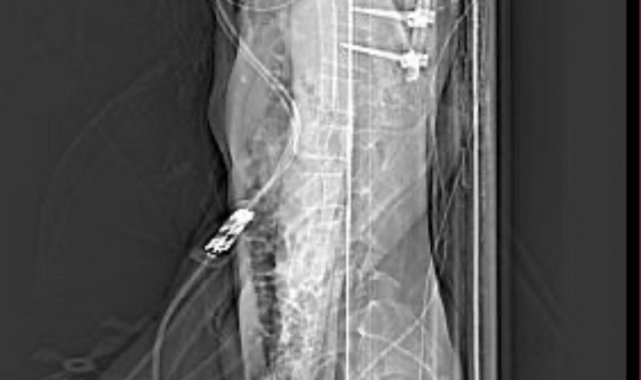

"Beş gün entübe edildi. Ne olacağı belli değildi çıkmama ihtimali vardı. Şükürler olsun doktorlarımız ve Rabbim sayesinde entübeden çıktık. Hatta ciğerin birisinde infilak vardı; ciğer sorunumuzdan dolayı özellikle yoğun bakımda entübediydik. Beş günün sonunda ciğerleri toparlamaya başladı; entübeden çıkarttılar. Solunumu normale döndü. Sırayla sağlığı yerine gelmeye başladı. Bir hafta sonra kolundan ameliyat oldu platin koydular. Omurilikten ameliyat olduk. Omuriliğinde ilk röntgende tek kırık gördüler; üç kemiği birbirine bağlayacaklardı. Sonradan ikinci röntgende üç kırık olduğunu gördük; yedi kemiği birbirine bağladılar. Omuriliğe platin takıldı. 14 tane civatamız var. Şükürler olsun doktorlarımıza, Allah razı olsun. Evladımız gayet iyi, sağlıklı, yerinde. Artık işte suratta, çenede, burunda, elmacık kemiklerinde parçalı kırıklarımız var. Osman Gazi Fakültesi'nde Allah'ın izniyle buradaki hocalarımıza, önce Rabbim'e sonra hocalarımıza emanet çocuğumuz. İnşallah daha iyi olacağız; ben kendi adıma söylüyorum. Çocuğuma, her motora bindiklerinde sürekli kask ve montlarını giymelerini tembihliyordum. Giymediklerinde fırça atıyordum. Eskişehir'de birçok yerde tanınırız, tanırlar. Sevenimiz, eşimiz, dostumuz çok; uyarırlar, telefon gelir, haber verirler. Her duyduğumda, gördüğümde söylerim. Sağ olsun, çocuğum da o gün beni dinlemiş, kaskını takmış. Şükürler olsun ki takmış; takmasaydı o gün, o kazada belki çocuğumuzu kaybederdik."